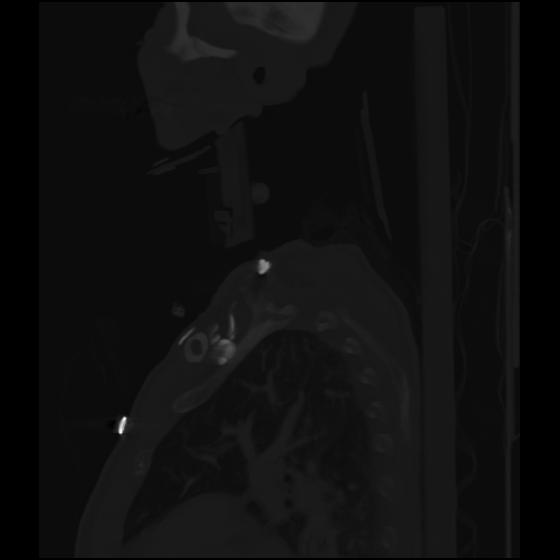

24 ANGIO,CE,Sag-MIP,5.000,ANGIO,Sag-MIP,